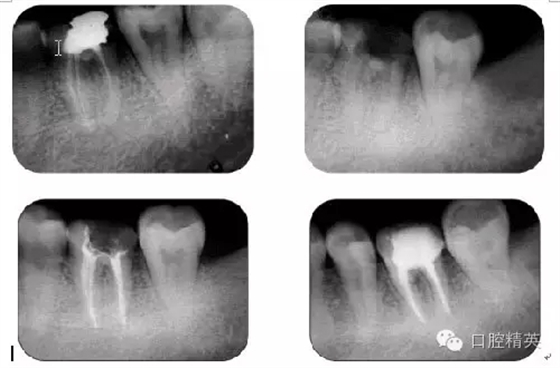

病例1:常規(guī)根管治療